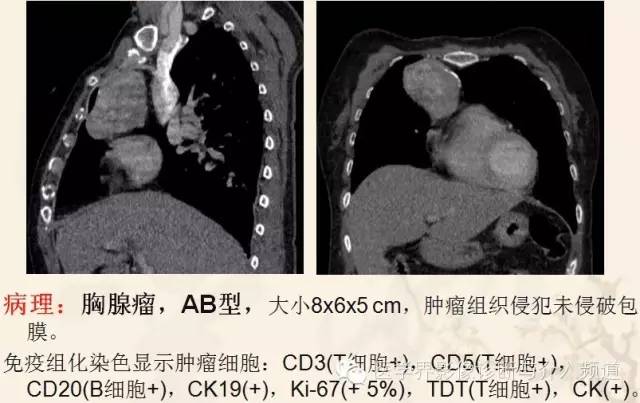

胸腺瘤(Thymoma)

近期WHO依胸腺瘤的上皮细胞形态及其与淋巴细胞比例,将其分为A型、AB型、B型和C型,该分型可作为独立预后因素,并与肿瘤侵袭性、复发等密切相关。

良性胸腺瘤:多为圆形或类圆形实质性肿块,有包膜,边界光滑,密度均匀,增强扫描轻至中度强化,与周围组织结构分界清晰,周围脂肪间隙显示良好,肿瘤与邻近结构之间通常有一低密度透亮带。

恶性胸腺瘤:肿瘤呈软组织肿块,形态多不规则,可呈分叶状,内部密度不均匀,囊变坏死多见,少数可见钙化,增强扫描多数呈不均匀强化,大血管被挤压、推移或包绕,部分可见肿瘤突入血管内。